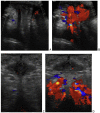

Nutcracker phenomenon is the descriptor for a patient's anatomy whenever the left renal vein becomes compressed between the abdominal aorta and the superior mesenteric artery. Nutcracker syndrome is the terminology used when the nutcracker phenomenon is accompanied by symptoms including pain (abdominal, flank, pelvic), hematuria, and orthostatic proteinuria. Diagnosis can be made with Doppler ultrasound, venography, computed tomography, or magnetic resonance imaging. This case demonstrates some of the typical findings of nutcracker syndrome. The limited clinical features and interesting imaging findings, in addition to the young age of the patient, make this a notable case.